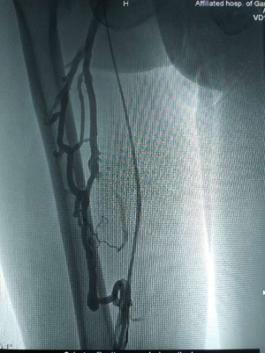

行“右下肢静脉造影”,见右侧胫前、胫后、腓静脉近心端,腘静脉、股浅静脉充盈缺损,大小隐静脉扩张,股深静脉侧支开放,股深、股总、髂静脉通畅。

术前造影